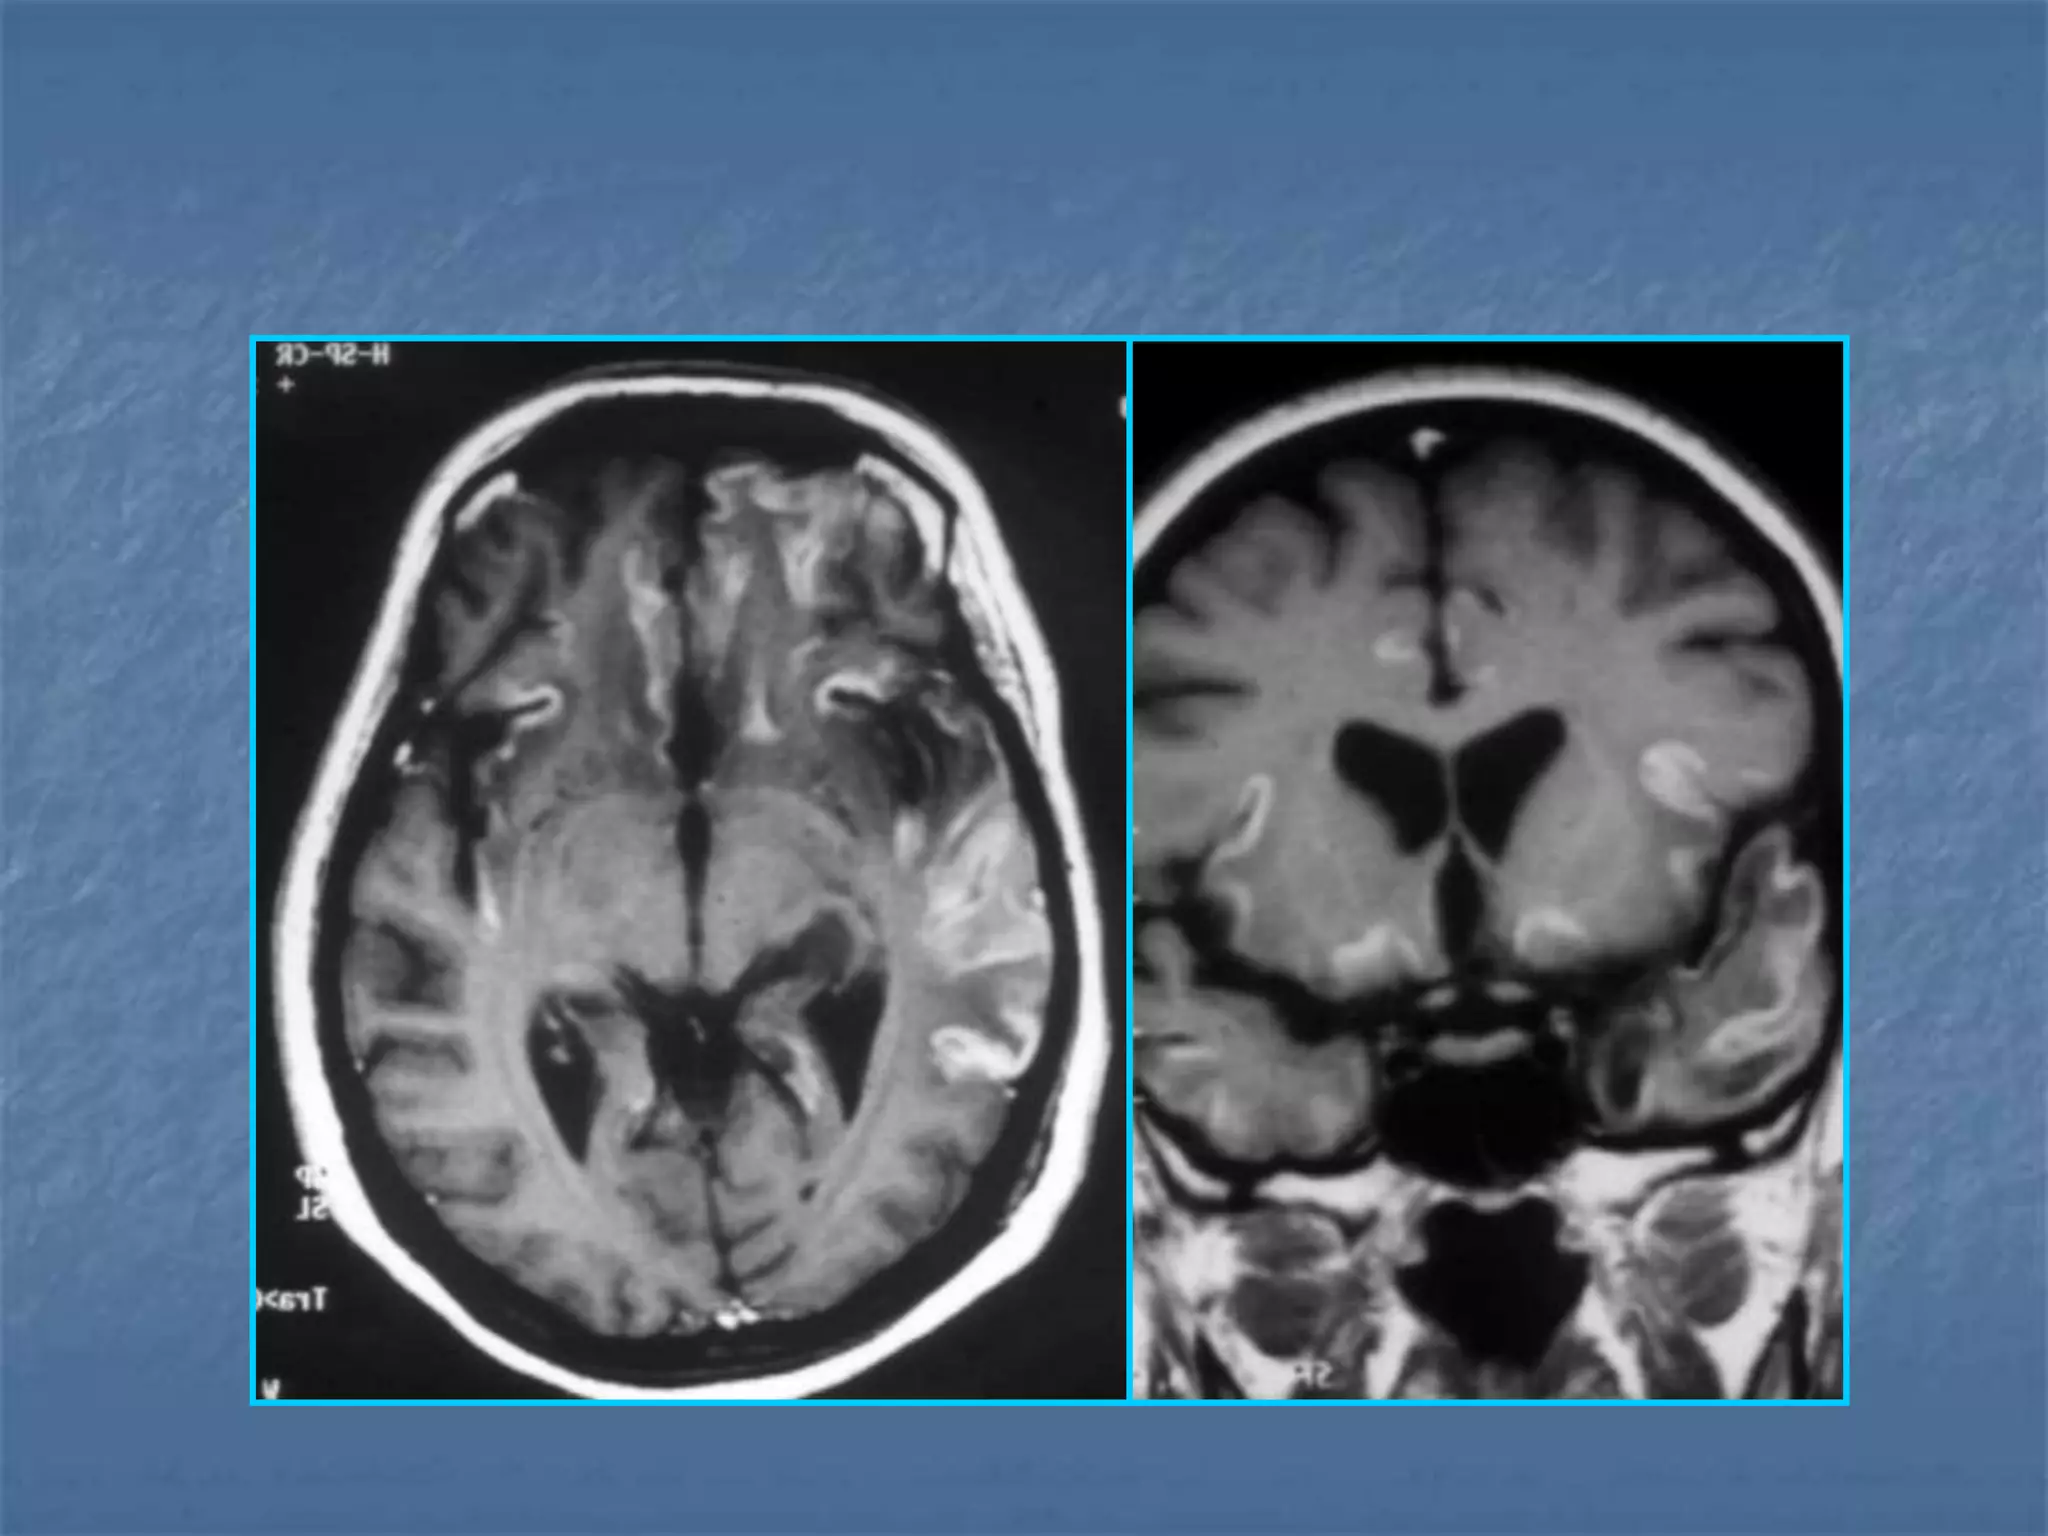

ACUTE ON CHRONIC SDH